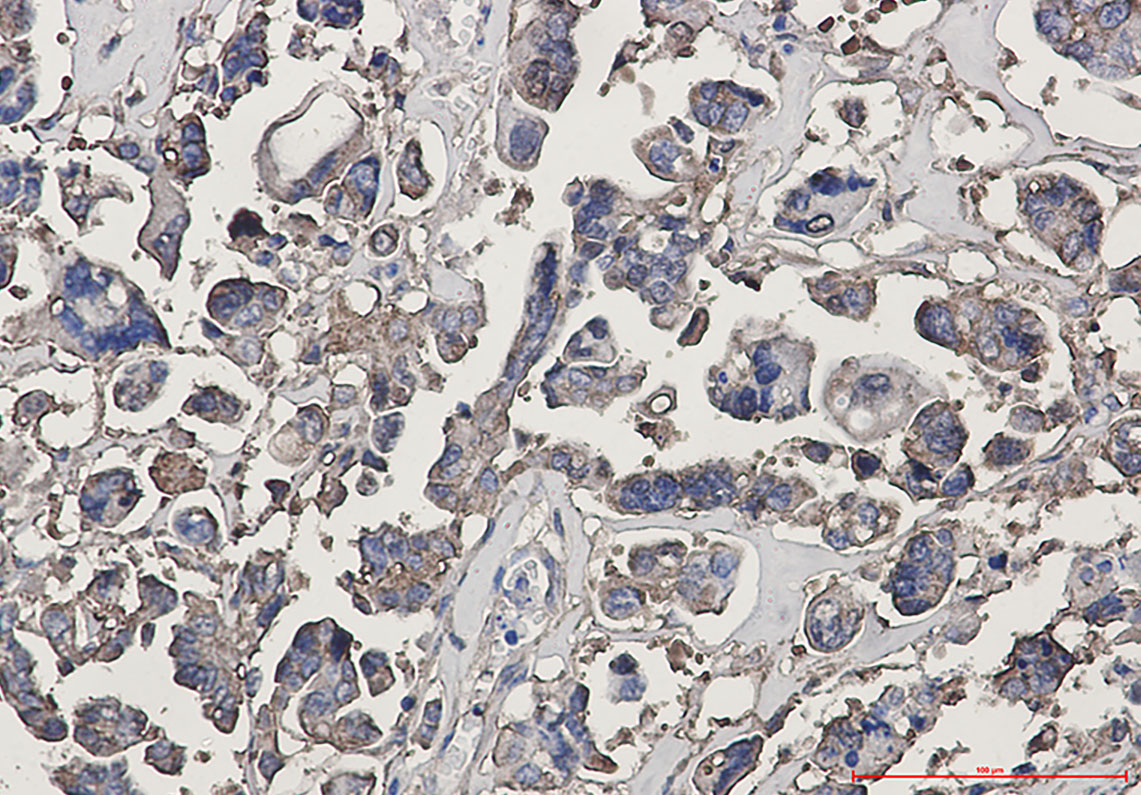

beta III Tubulin Rabbit mAb

| Dilution | WB~~1:1000-1:5000 IHC-P~~1:50~200 FC~~1:20 |

| Tissue Location | Expression is primarily restricted to central and peripheral nervous system. Greatly increased expression in most cancerous tissues. |